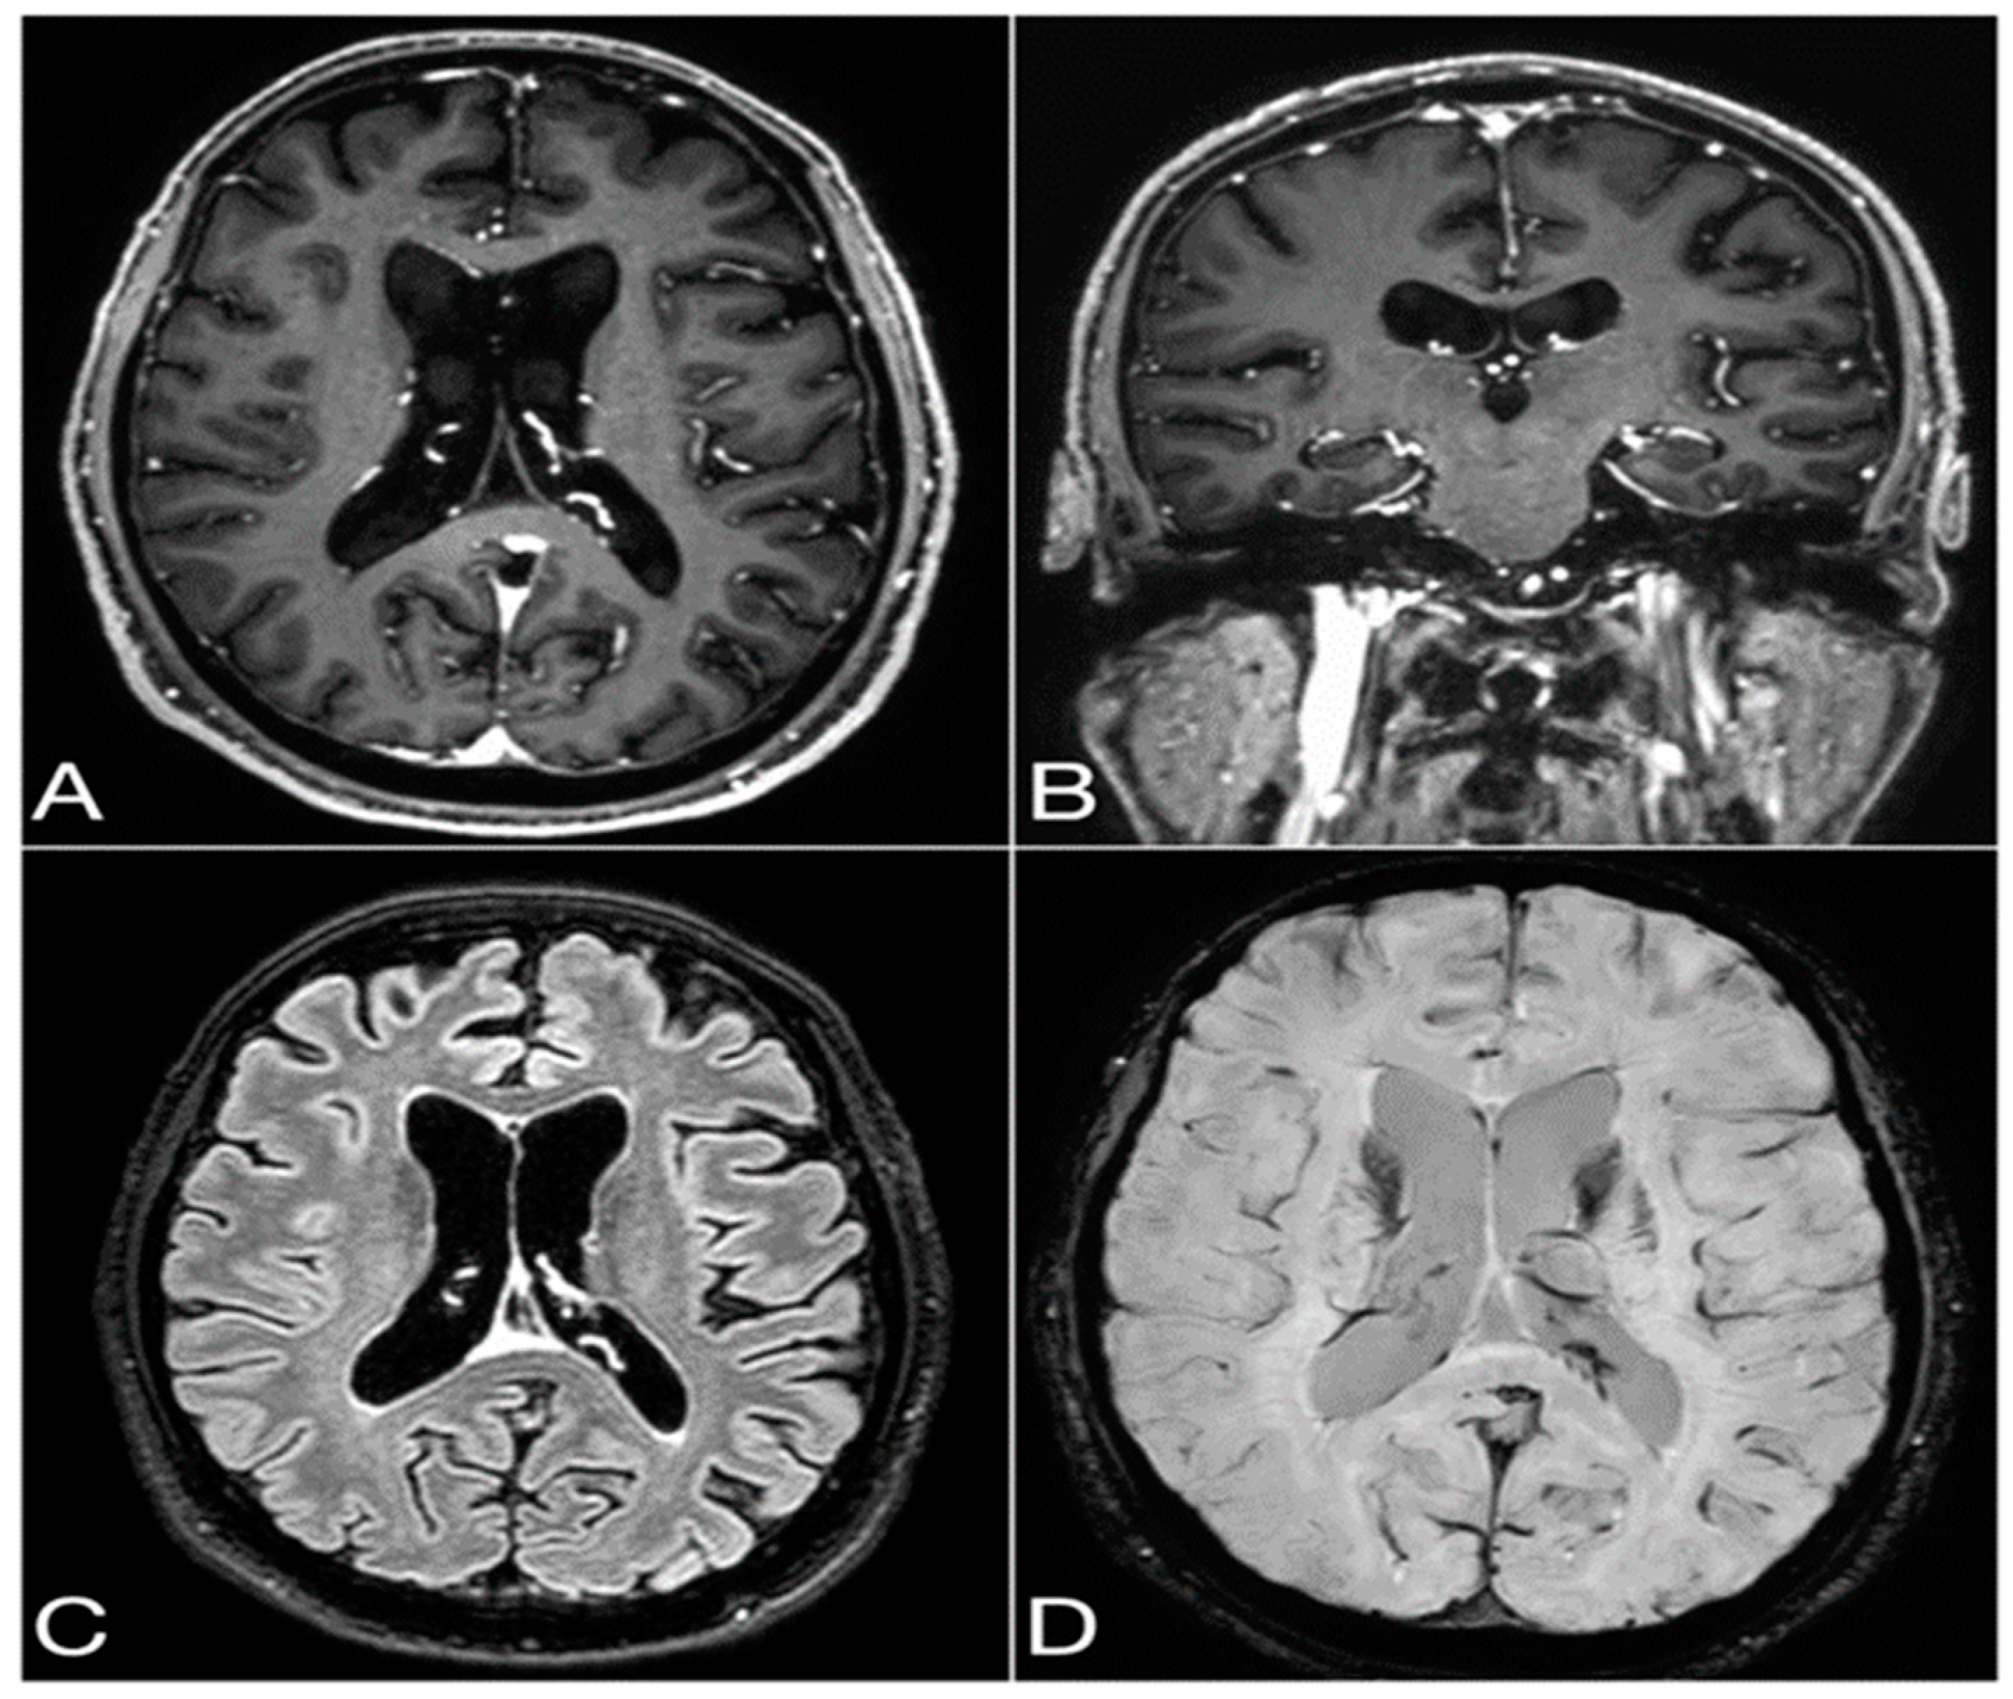

2.2. Diagnostic Findings